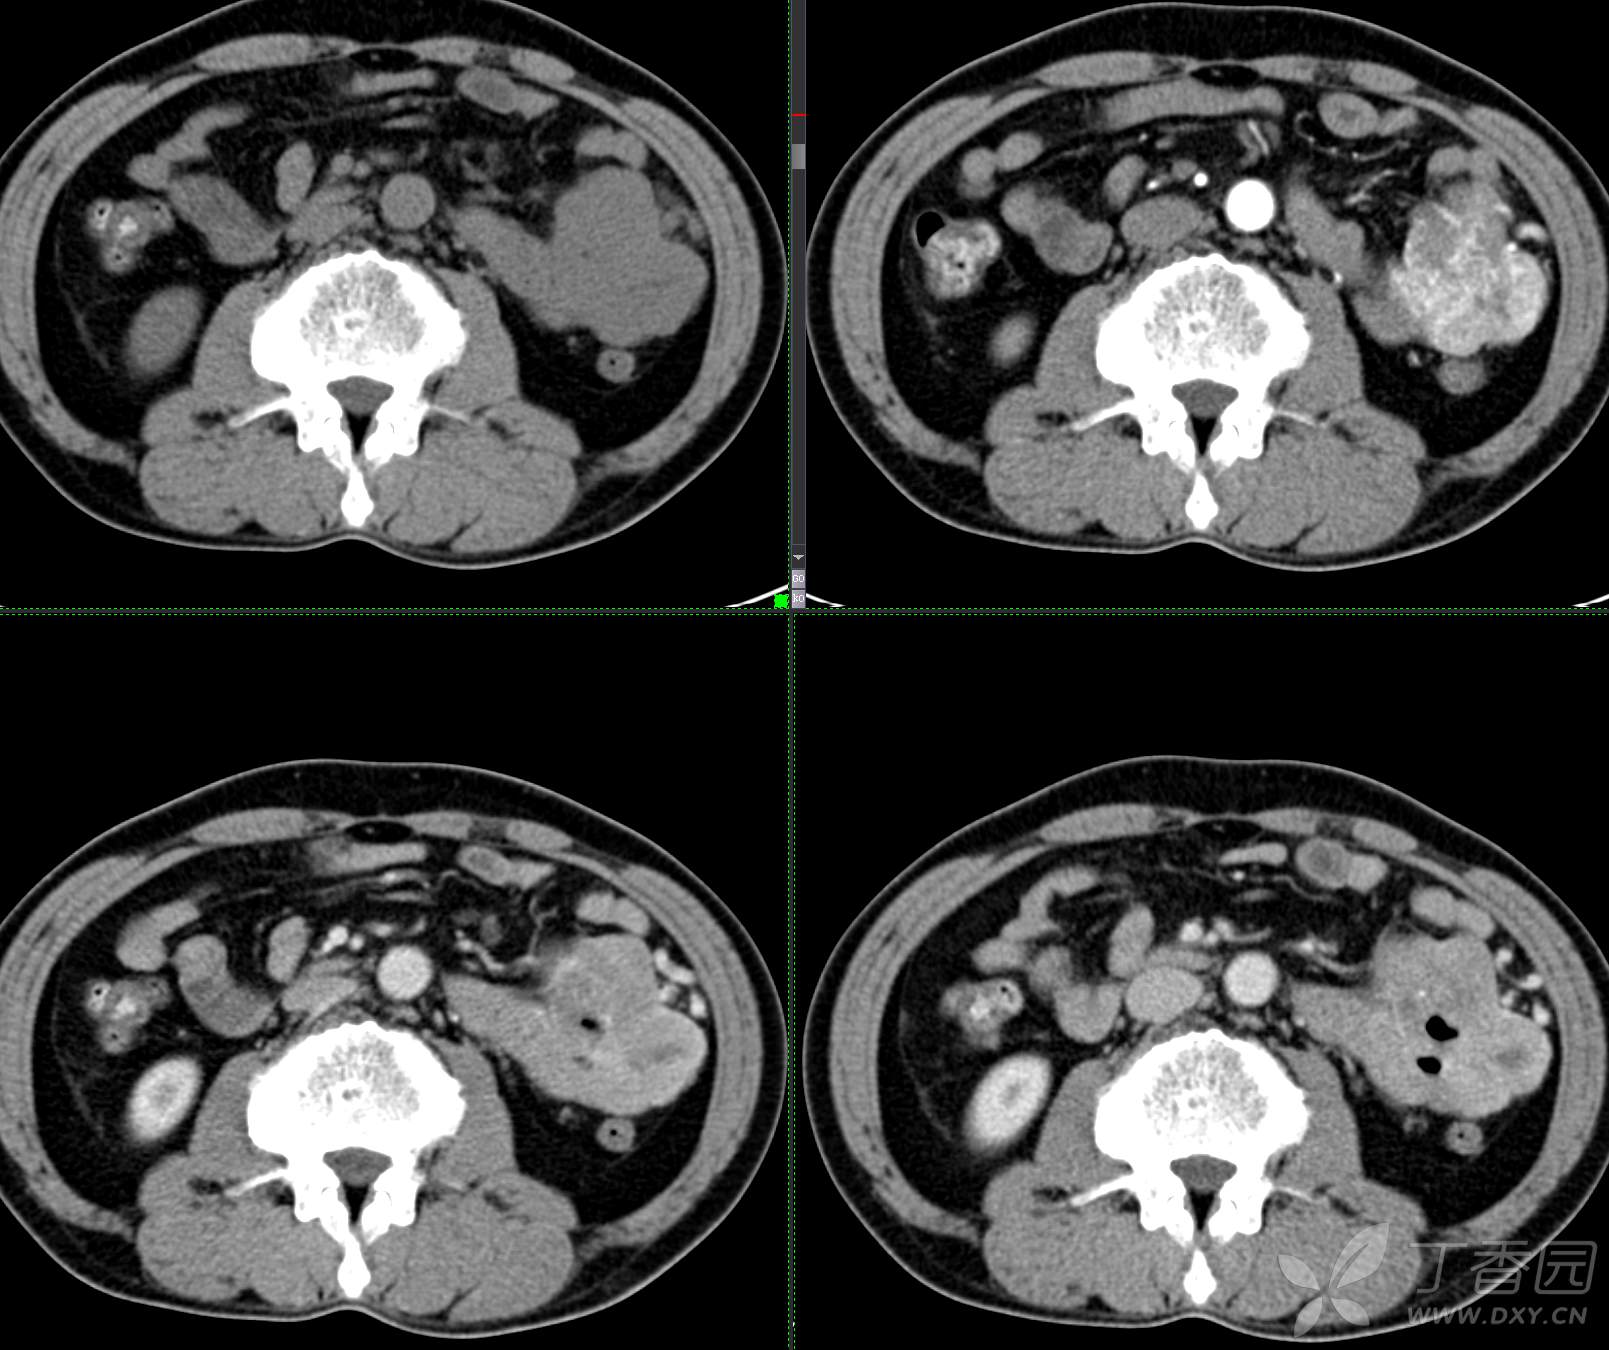

讨论:小肠病变,间质瘤?淋巴瘤?小肠腺癌?